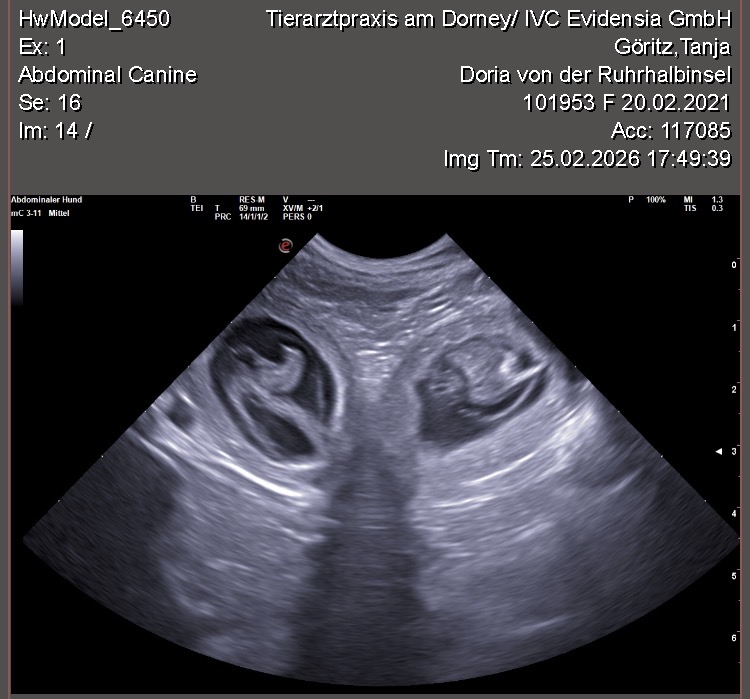

Wir waren erfolgreich und konnten Fruchtanlagen mit schlagenden Herzen sehen. Wir gehen zum aktuellen Zeitpunkt wieder von einem größeren Wurf aus. Daykos und Dorias Rendevouz war also sehr vielversprechend!

Hier zeigen wir euch einige der kleinen gefüllten Fruchtblasen mit Inhalt und schlagenden Herzen. Da wir kurz vor Ostern mit der Geburt rechnen, nennen wir sie „Ostereier“ 🙂